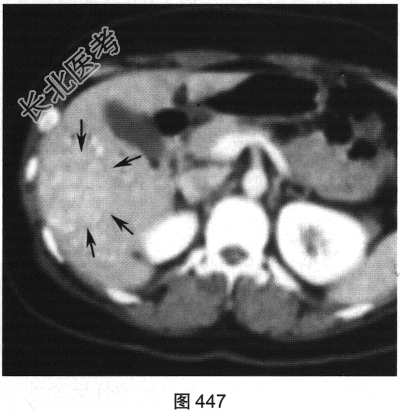

- 多项选择题2.[提示]患者行CT三期增强扫描,如图446~图448所示。对患者CT三期增强扫描图像描述正确的是( )

A、动脉期病灶明显强化

B、门脉期病灶无强化

C、病灶位于肝S5/6,边界清

D、延迟期病灶呈等密度

E、病灶为富血供肿瘤

F、门静脉期病灶为低密度